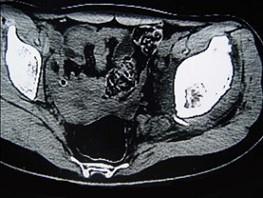

问题 患者,女,19岁,左髋疼痛、活动受限伴跛行6个月,无发热、盗汗病史,曾考虑左髋关节结核并抗结核治疗2周,症状有一定缓解,请结合所提供图像,选择最佳答案 ( )

选项 A、骨化性纤维瘤 B、骨囊肿 C、非骨化性纤维瘤 D、软骨母细胞瘤 E、骨样骨瘤

答案 D